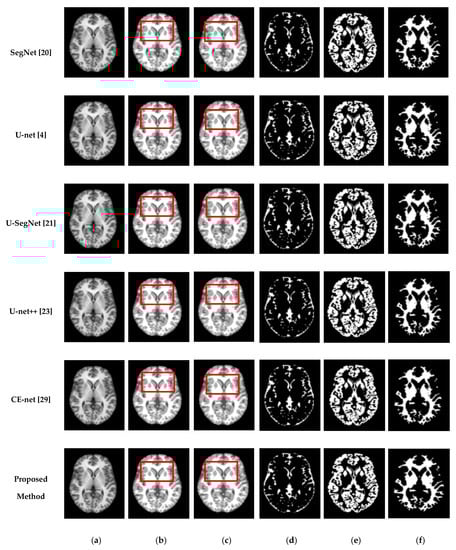

Figure 5 and Figure 6 show the segmentation results for the axial, coronal, and sagittal planes of the OASIS and IBSR datasets, respectively. The figures show that the proposed approach achieves well-segmented performances for GM, WM, and CSF of the brain MRI on both datasets. The axial plane shows the most informative details in the central slices of the MRI compared to the other planes. Thus, the segmentation results for the axial planes show the segmentation performance most effectively. In addition, the highlighted boxes in Figure 5 and Figure 6 show that the quality of sagittal and coronal images is highly promising without any difference in every detail. From the results of Figure 5 and Figure 6, it can be inferred that the proposed method can extract complicated pattern features from all three planes.

Figure 6.

Segmentation results for the axial, coronal, and sagittal planes of the brain MRI image (top to bottom) on the IBSR dataset using the proposed method. (a) Original input images, (b) ground truth segmentation map, (c) their predicted segmentation map obtained by using the proposed method, (d) predicted GM (binary map), (e) predicted CSF (binary map), (f) predicted WM (binary map).